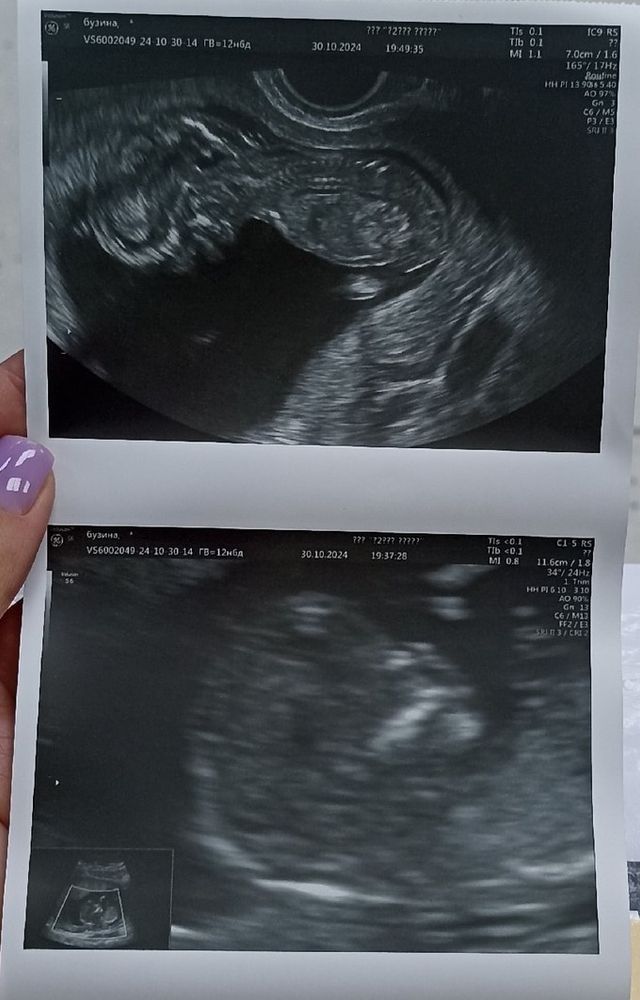

Анализы, скринингиДобрый день форумчане! Попробую рассказать свою историю прохождения первого скрининга в Центре Пренатальной диагностики на Екатерининской, 85, г. Пермь. Первый скрининг был назначен на 23.10.2024 г. Вход без мужа, о желании получить снимок-предупреждать заранее, фото платное. Я конечно согласилась. Осмотр прошел спокойно, врач молча выполняла свои манипуляции, я с интересом смотрела на монитор висящий для меня на стене. По итогу осмотра, врач сказала, что все хорошо, только у малыша будет маленький носик, пока я одевалась, она еще раз увеличила фото, приготовленное для печати и мерила косточки на носике. Я получила результаты УЗИ (на фото) без всяких дополнительных комментариев и вышла в соседний кабинет сдавать кровь, там сказали, что если в течении пары дней не позвонят, значит все хорошо с кровью. После сдачи крови оплатила фото и забрала снимок.

Только садясь в машину и прибирая документы в папку я увидела расчет рисков. СД 1:83!!!! носовая кость-отсутствует, но как же так, ведь я ее видела и на фото она есть. Земля ушла из под ног. Как так, почему врач промолчала, почему риски рассчитаны, когда результаты крови еще неизвестны. И если такие риски только по узи, то что будет когда придут риски по крови....Столько вопросом разом свалилось.

И вот ровно через неделю, успевая в сроки первого скрининга, мы уже вместе с мужем смотрели на нашего малыша и с замиранием сердца и ждали, что скажет врач. Вердикт - кости все на месте, носик просто прелесть, как можно было не увидеть наличие костей в первый скрининг-не понятно.